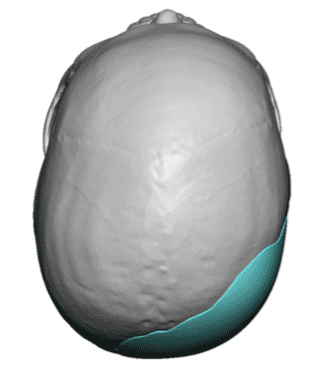

Patient 10

Desire to build up the flatter upper part of the back of his head.

Upper occipital skull augmentation using a custom skull implant.